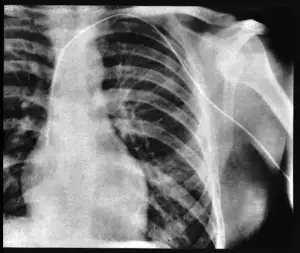

Primeras aplicaciones médicas de los rayos x

En el diagnóstico y tratamiento

• Bammes demuestra la radiografía de tórax con ranura